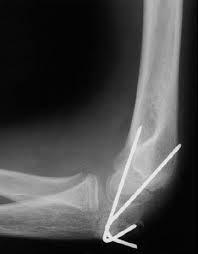

Elbow Fracture

How long does bone healing take? Many people with shoulder or elbow fractures don't need surgery. The most common complication after an elbow fracture (with or without surgery) is stiffness. Go to physical therapy as directed. It usually takes approximately 6 weeks for the fracture to fully heal. Then go through physical therapy. As a broken elbow heals, this new bone may form in areas where bone does not usually grow. In some circumstances your surgeon may recommend an operation either to fix the bone, replace it with an artificial radial head or to excise fragments of bone.